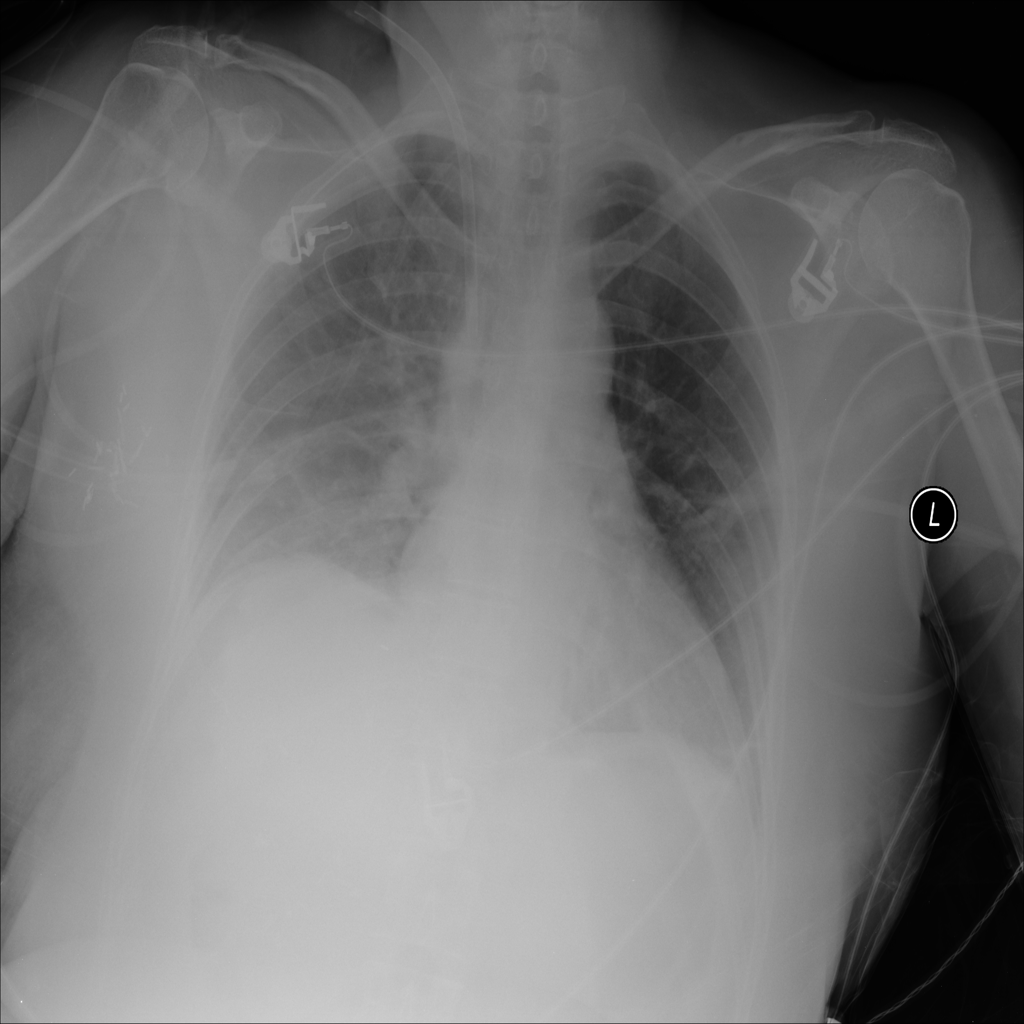

PAT-E81B · IMG-000Effusion

PAT-E81B · IMG-000

PA